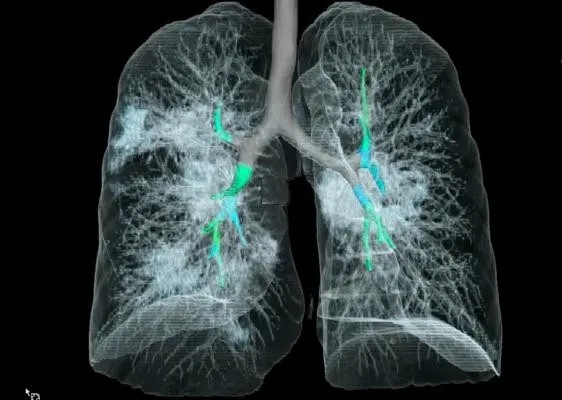

采用CT三维成像技术,

暴露在人们裸眼眼前,

到处是斑片状磨玻璃影(见下图)。